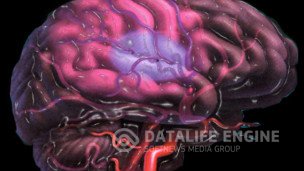

Инсульт ишемическийДля развития ишемического инсульта и размягчения мозговой ткани обычно требуется не полное прекращение... Инсульт ишемическийДля развития ишемического инсульта и размягчения мозговой ткани обычно требуется не полное прекращение...